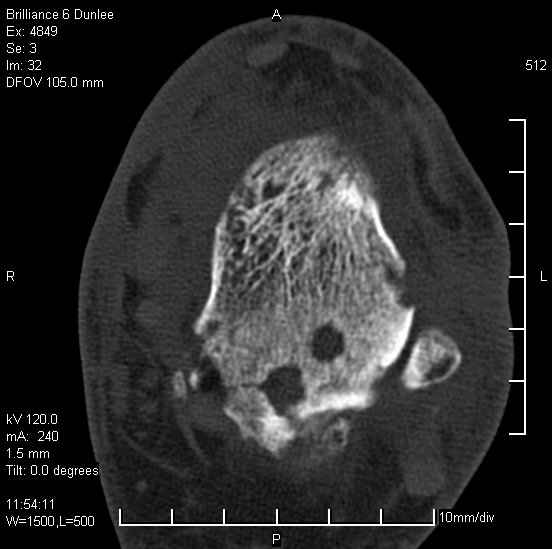

Асептический некроз таранной кости.

На лечении находится пациент 35 лет. Травма в сентябре 2008 г.- открытый вывих таранной кости

В день травмы ПХО, вправление вывиха, трансартикулярная фиксация. Рана зажила первично. С января нагрузка на конечность. С конца апреля- болевой синдром. На рентгенограммах и КТ признаки ас. некроза таранной кости, артроз подтаранного и голеностопного суставов.

У больного тотальный ас. некрох блока таранной кости, заинтересованы голеностопный и подтараный суставы. Эндопротезирование маловероятно на некротизированную кость. Изолированный подтаранный артродез таран не спасет.При артродезе всю некротизированную кость придется убрать.А далее замещение либо за счет большеберцовой кости, или удлинение на регенерате.